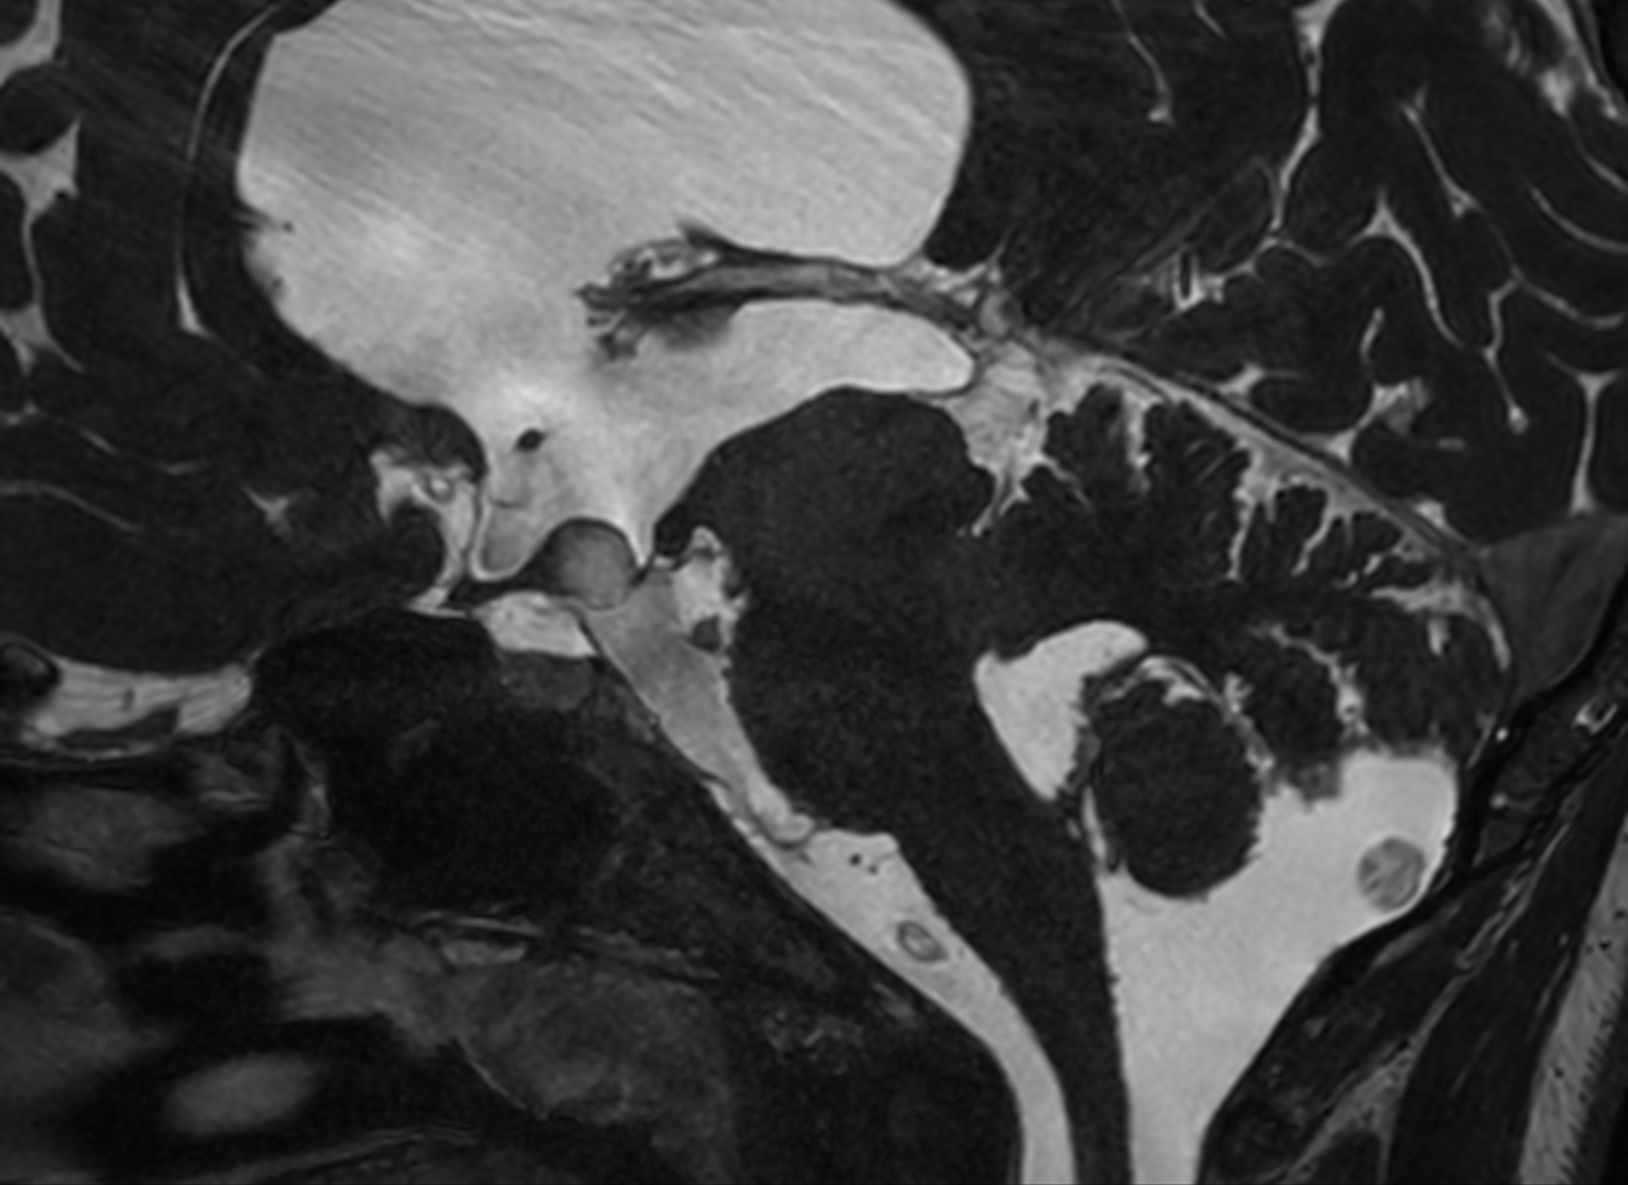

Sagittal 3D T1w TFE